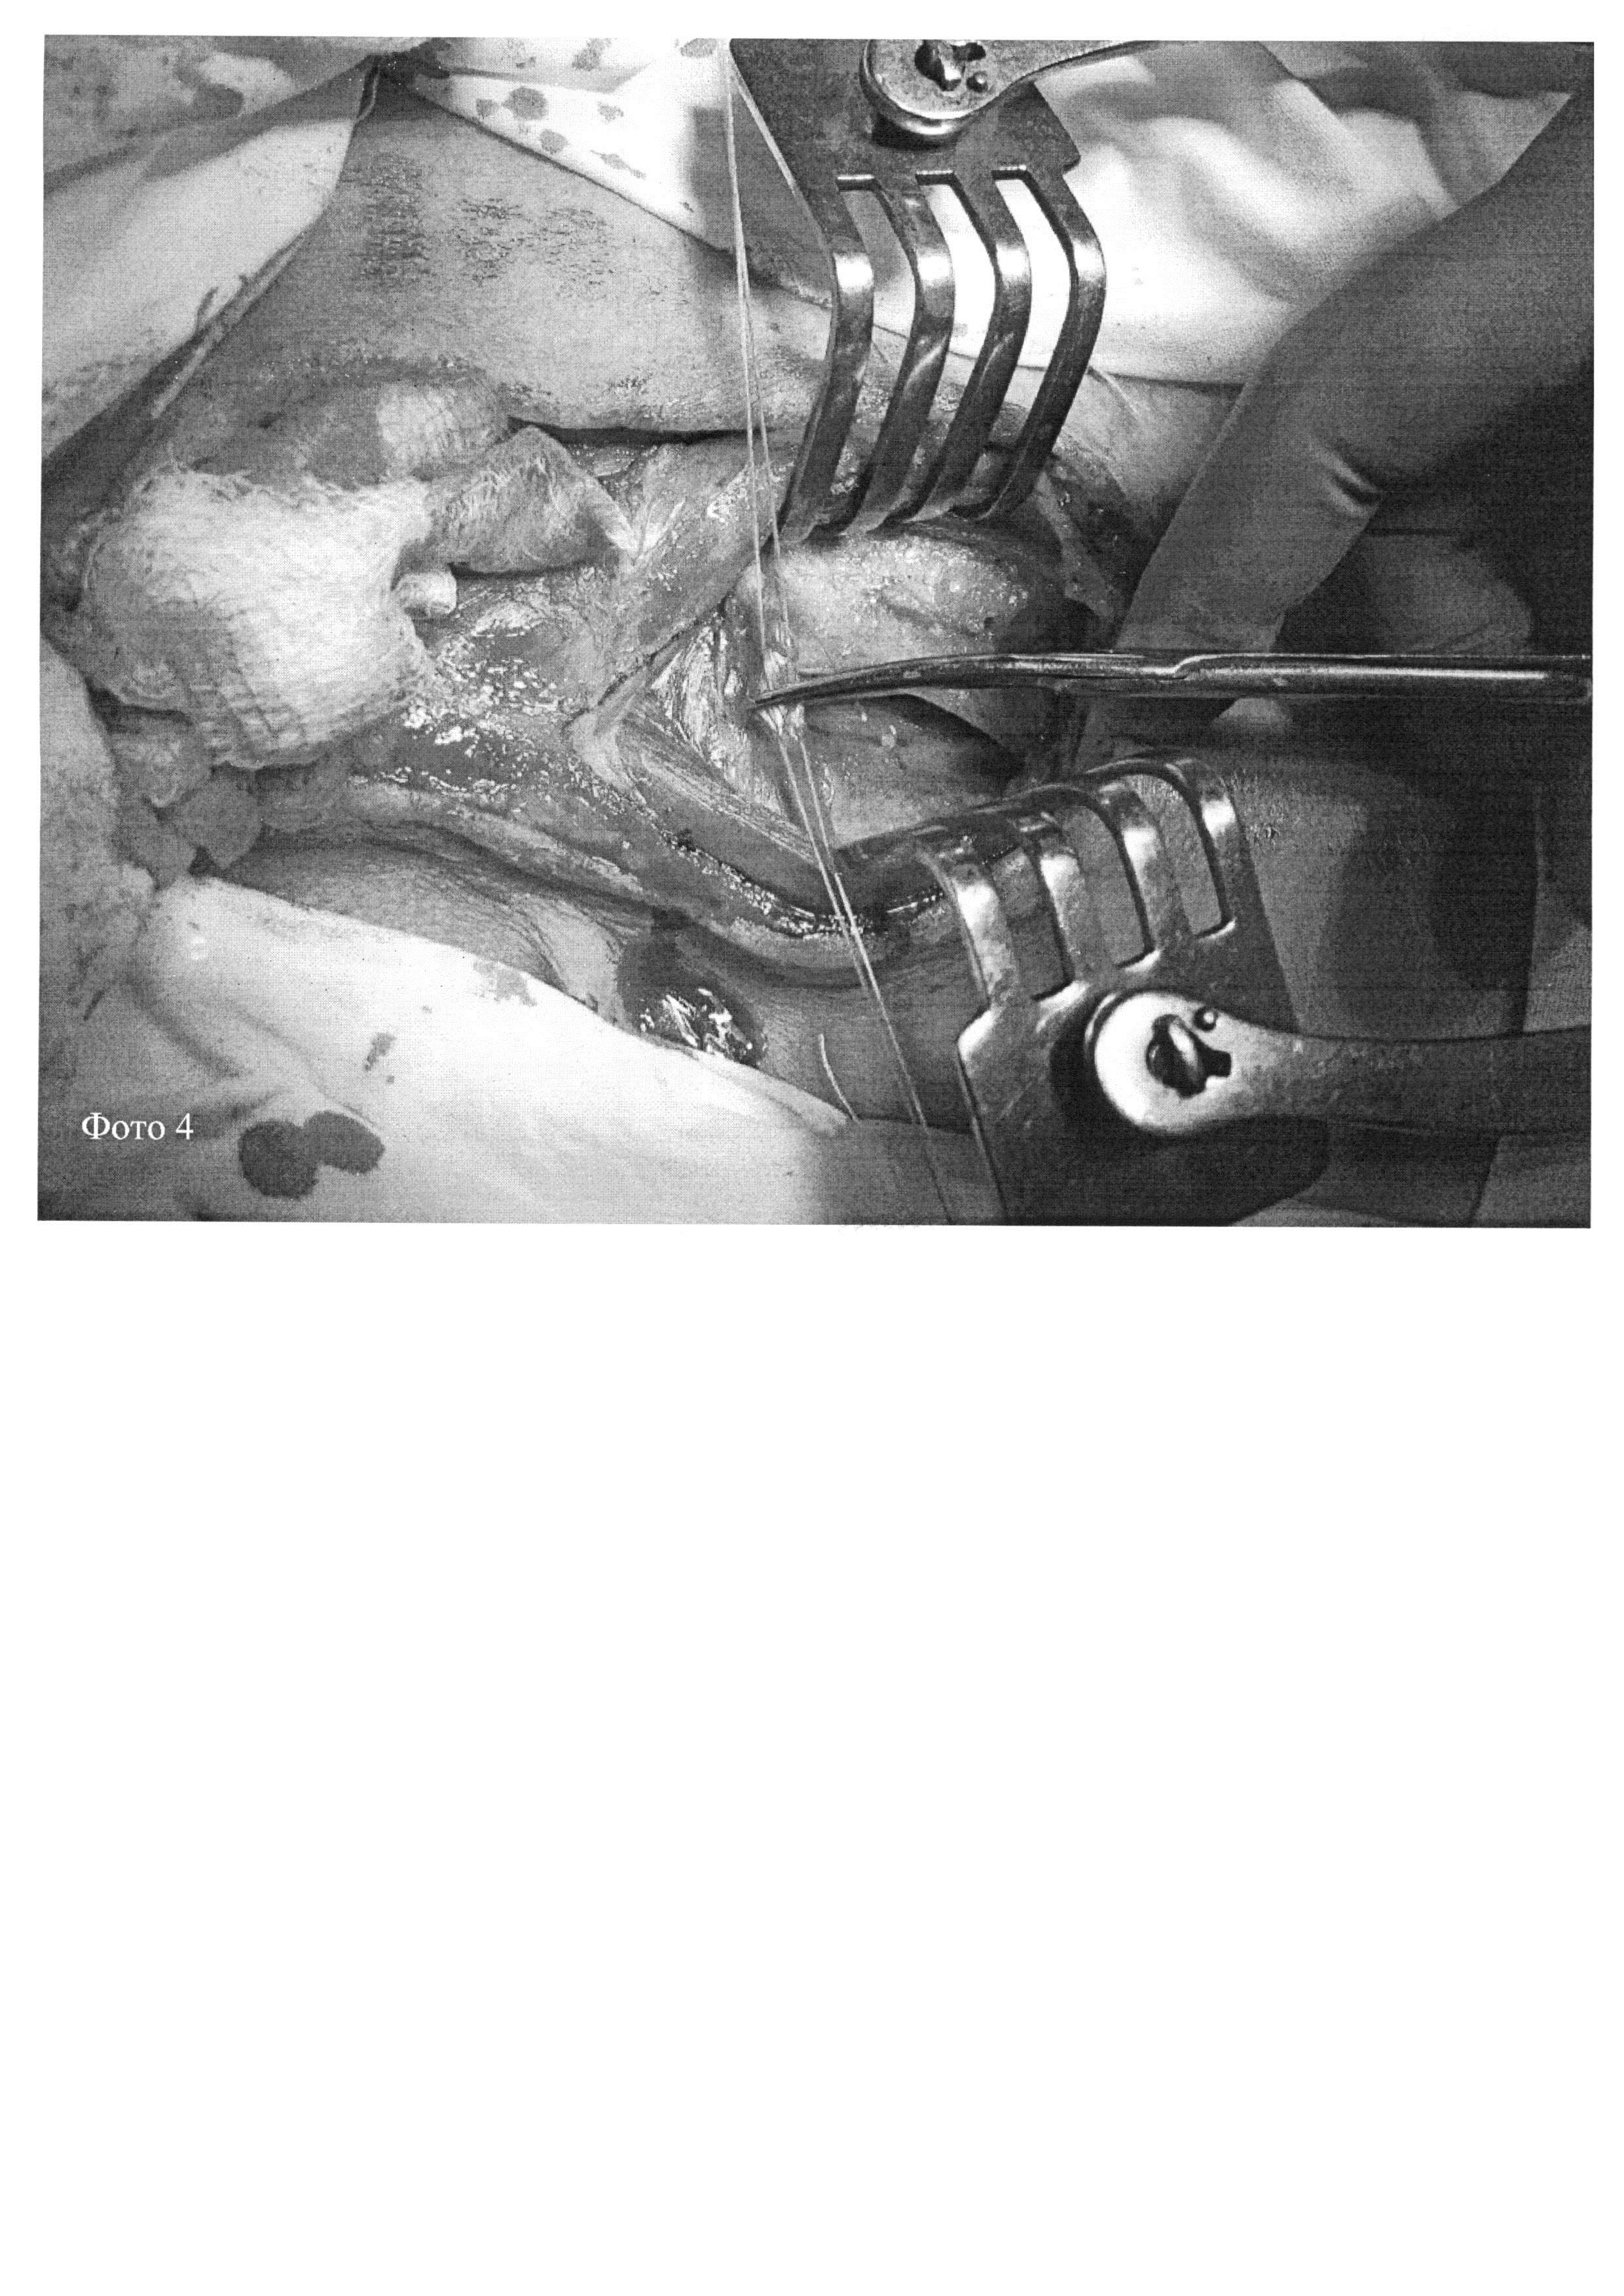

Предлагаемый способ осуществляется следующим образом: под общей анестезией, косо-продольным разрезом, начиная от грудино-ключичного сочленения и далее до сосцевидного отростка, рассекается кожа, подкожная жировая клетчатка и m. platisma (фото 1, 2). В в/3 раны ранорасширителем кивательная мышца отводится вместе с внутренней яремной веной кнаружи. Выделяется дистальный отдел общей сонной артерии, внутренняя и наружная сонные артерии (фото 3). Далее ранорасширителем в н/3 раны раздвигаются ножки кивательной мышцы без пересечения. При необходимости (не всегда) рассекается лопаточно-подъязычная мышца на уровне сухожилия после предварительного наложения швов-держалок. Передняя лестничная мышца вместе с диафрагмальным нервом и внутренней яремной веной отводятся кнаружи. Выделяется 1-й сегмент подключичной артерии, позвоночная и внутренняя грудная артерии. Артерии берутся на держалки (фото 4, 5). Первым этапом выполняется подключично-сонная транспозиция (фото 6), вторым каротидная эндартерэктомия из ВСА (фото 7). При невозможности выполнить подключично-сонную транспозицию (распространенное поражение до 2-го сегмента, перегиб позвоночной артерии из-за анатомических особенностей) выполняется сонно-подключичное шунтирование, что может потребовать расширения операционного доступа в виде частичного пересечения медиальной части передней лестничной мышцы. При ушивании раны пересеченное сухожилие лопаточно-подъязычной мышцы ушивается сужильным швом. Далее послойное ушивание раны с оставлением дренажей активной аспирации (фото 9).